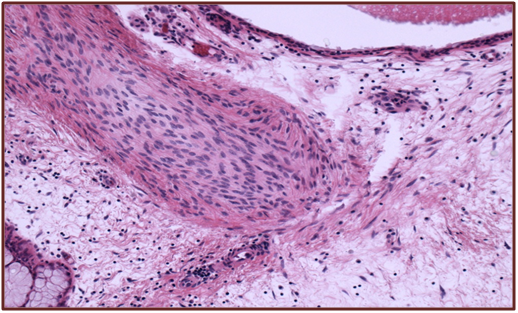

Histologically COREAH of the nasal cavity is characterized by features of a respiratory epithelial adenomatoid hamartoma (REAH) with elements of cartilaginous tissue and /or bony trabeculae. The adenoid components in COREAH tend to be less prominent compaired to REAH whilst immunohistochemistry isunremarkable.1,2

A 66 year old woman presented to the department of otolaryngology with complains of chronic headaches, rightnasal obstruction, and midfacial pain with a duration of 3 years. Clinical examination with a rigid endoscope revealed a polypoidal mass like structure in the right nasal cavity, extending from the middle turbinate to the posterior nasal space. CT and MRI depicted a soft tissue mass with calcification developing in the right nasal cavity, with no signs of bone erosion. The mass had a cephalocaudal diameter of 5 cm and a maximum anterior-posterior diameter of 3 cm extending from the level of the middle and superior turbinate back to the nasopharynx occluding partly the sphenoid sinus ostium. The maxillary and frontal sinuses were unremarkable. The patient underwent functional endoscopic sinus surgery with complete tumor resection. During surgery a small specimen was sent for frozen biopsy histopathological examination in order to exclude evidence of malignancy. Postoperative course was uneventful. The submitted specimen had a smooth hard surface with small irregular fragments of soft and bony tissue. Microscopic evaluation revealed an epithelial component consisting of islands of respiratory type epithelium with polypoid configuration forming invaginations into the subepithelial loose fibrovascular myxoid stromaadmixed with areas of immature fibrocartilaginous and bony tissue. No atypia or mitoses were observed or signs of infiltrative growth, excluding malignancy (Figure1 & 2).

Figure 2 Chondrofibromatous areas.